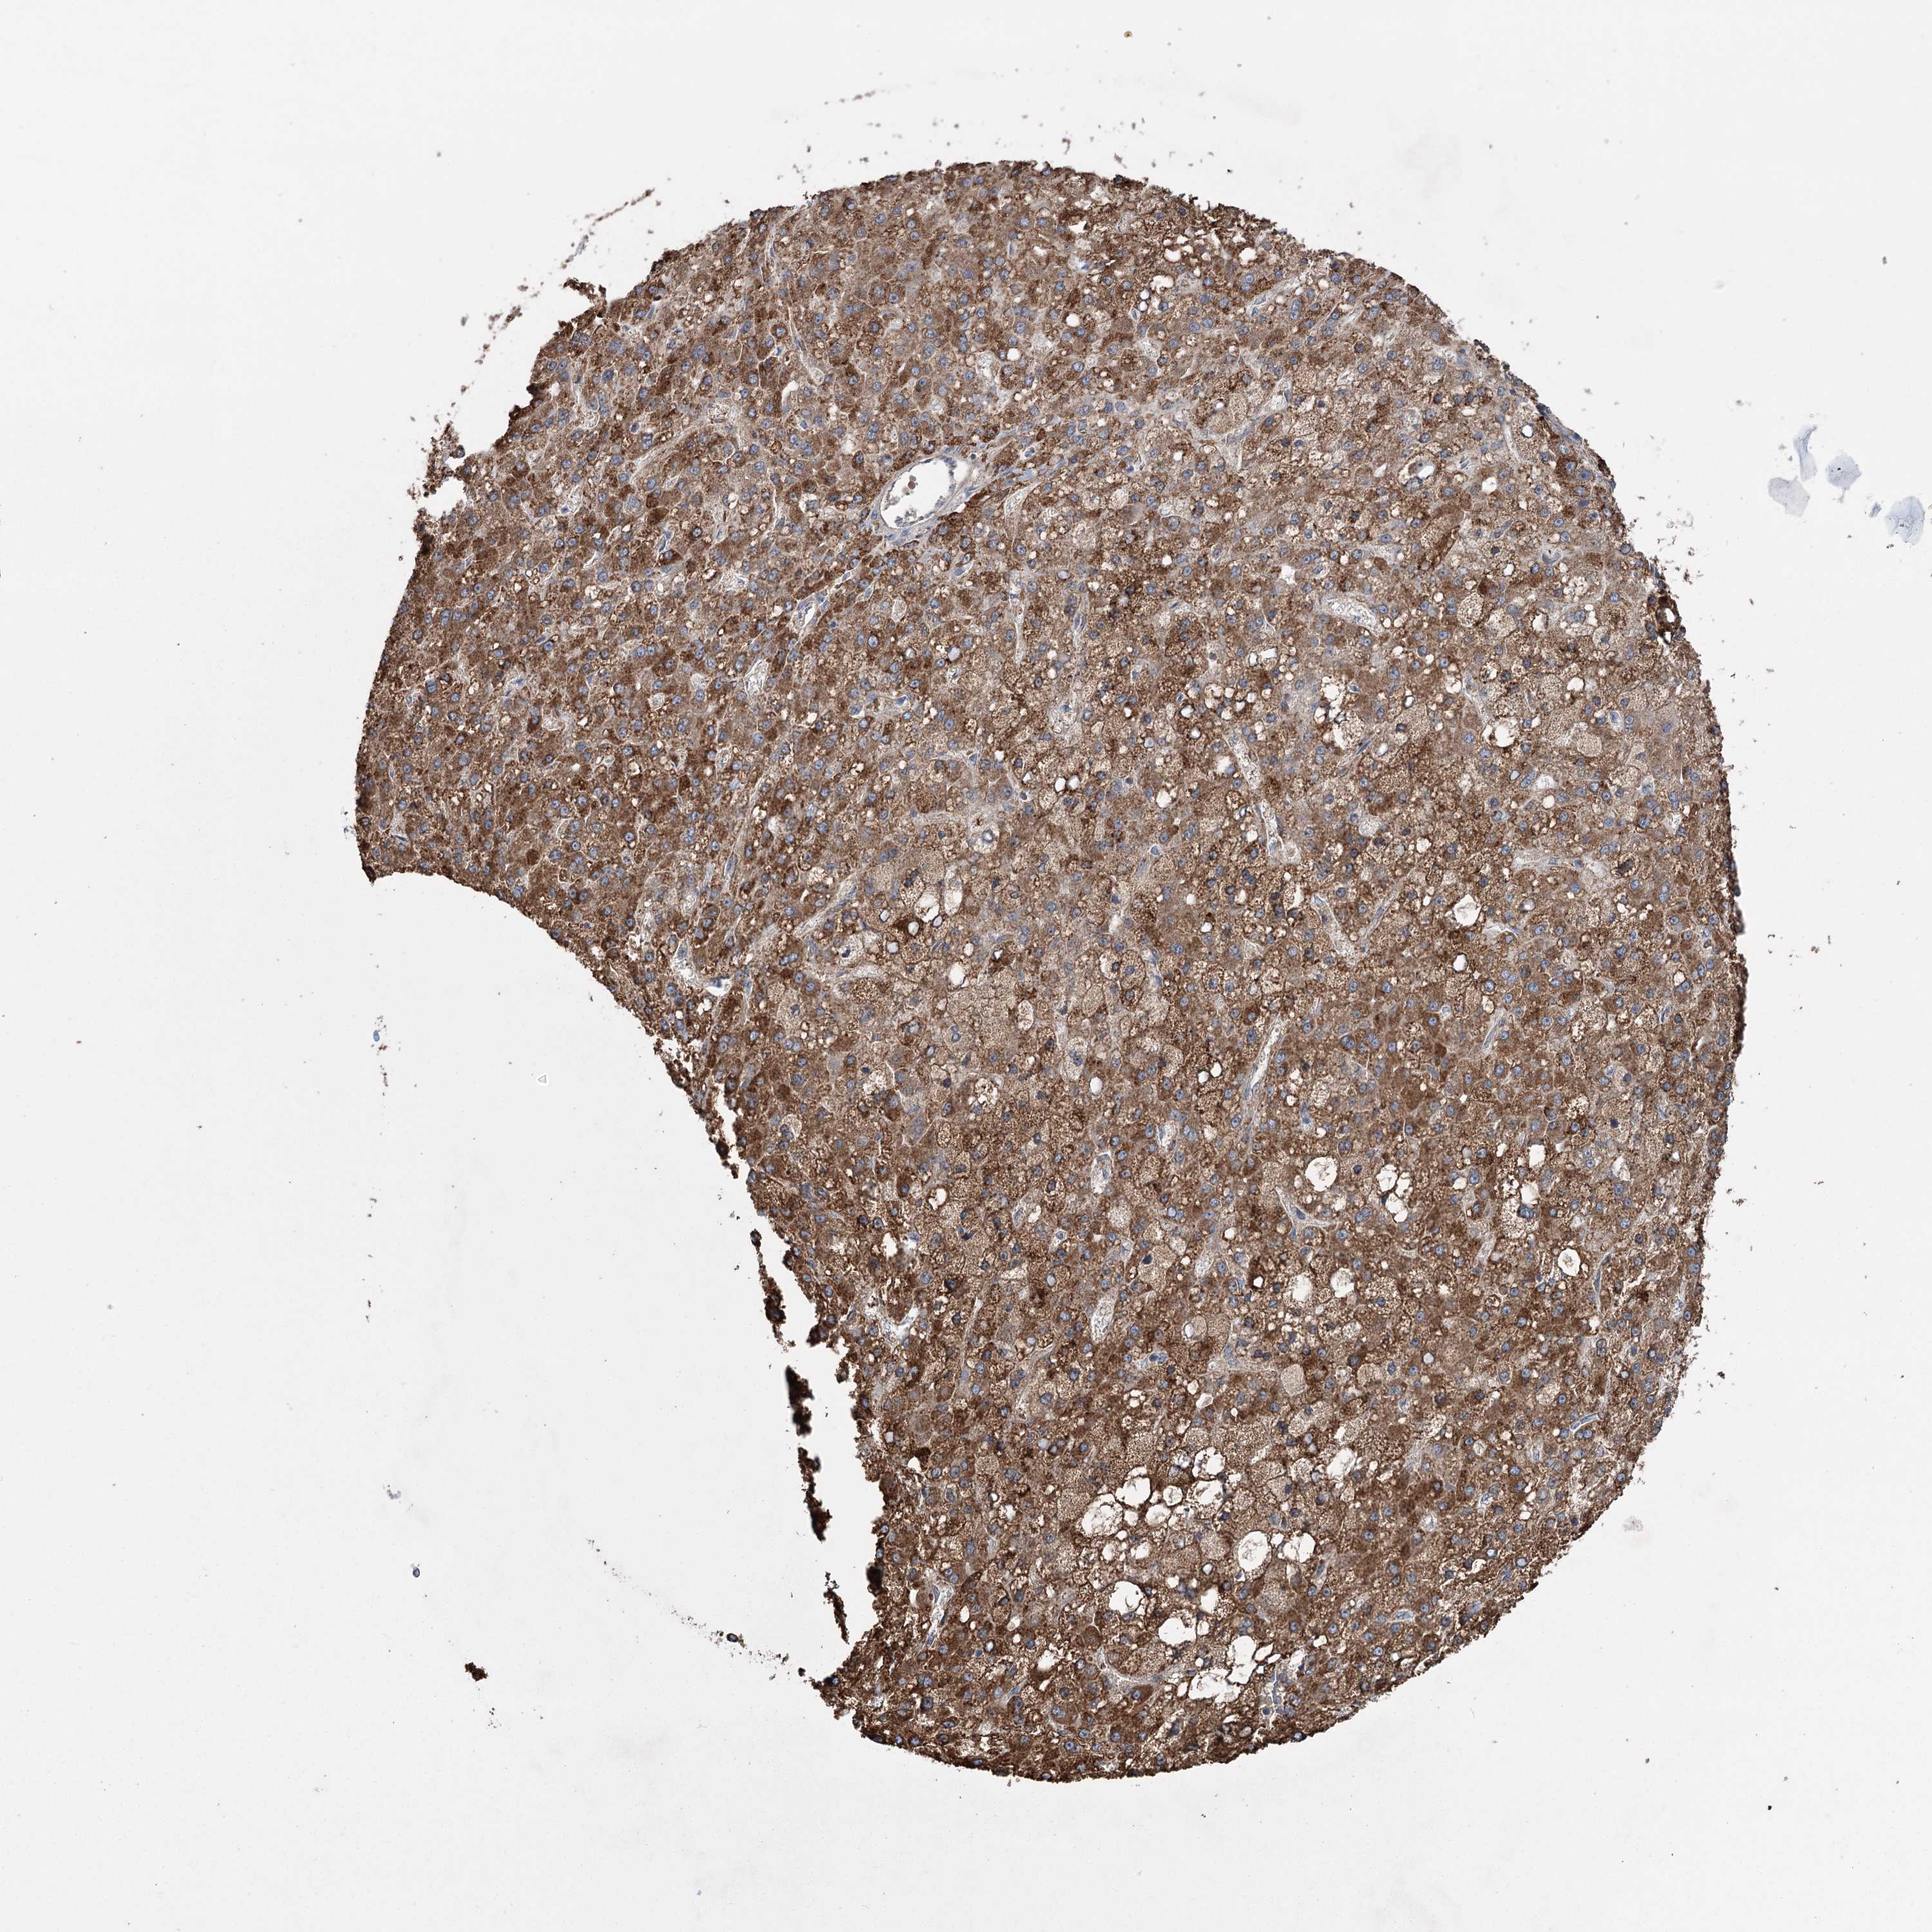

LIVER CANCER - Protein expressioni

A mouse-over function shows sample information and annotation data. Click on an image to view it in a full screen mode. Samples can be filtered based on level of antibody staining by selecting one or several of the following categories: high, medium, low and not detected. The assay and annotation is described here.

Note that samples used for immunohistochemistry by the Human Protein Atlas do not correspond to samples in the TCGA dataset.

Antibody stainingi

Antibody staining in the annotated cell types in the current human tissue is reported as not detected, low, medium, or high, based on conventional immunohistochemistry profiling in selected tissues. This score is based on the combination of the staining intensity and fraction of stained cells.

Each image is clickable and will lead to virtual microscopy that enables deeper exploration of all samples and also displays staining intensity scores, fraction scores and subcellular localization as well as patient and tissue information for each sample.

Antibody HPA038141

Antibody HPA038142

Staining

High

Medium

Low

Not detected

Intensity

Strong

Moderate

Weak

Negative

Quantity

>75%

75%-25%

<25%

None

Location

Nuclear

Cytoplasmic/membranous

Cytoplasmic/membranous,nuclear

Cholangiocarcinoma

Carcinoma, Hepatocellular, NOS